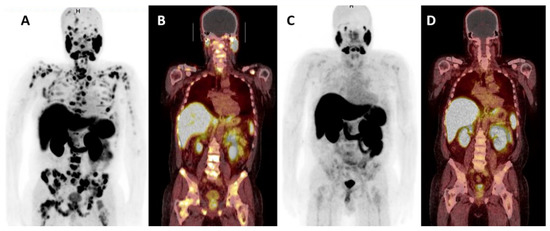

- Bakht, M.K.; Lovnicki, J.M.; Tubman, J.; Stringer, K.F.; Chiaramonte, J.; Reynolds, M.R.; Derecichei, I.; Ferraiuolo, R.; Fifield, B.; Lubanska, D.; et al. Differential Expression of Glucose Transporters and Hexokinases in Prostate Cancer with a Neuroendocrine Gene Signature: A Mechanistic Perspective for 18F-FDG Imaging of PSMA-Suppressed Tumors. J. Nucl. Med. 2020, 61, 904–910. [Google Scholar] [CrossRef] [PubMed]

- Spratt, D.E.; Gavane, S.; Tarlinton, L.; Fareedy, S.B.; Doran, M.G.; Zelefsky, M.J.; Osborne, J.R. Utility of FDG-PET in clinical neuroendocrine prostate cancer. Prostate 2014, 74, 1153–1159. [Google Scholar] [CrossRef]

- Parida, G.K.; Tripathy, S.; Datta Gupta, S.; Singhal, A.; Kumar, R.; Bal, C.; Shamim, S.A. Adenocarcinoma Prostate with Neuroendocrine Differentiation: Potential Utility of 18F-FDG PET/CT and 68Ga-DOTANOC PET/CT Over 68Ga-PSMA PET/CT. Clin. Nucl. Med. 2018, 43, 248–249. [Google Scholar] [CrossRef]

- Perez, P.M.; Hope, T.A.; Behr, S.C.; van Zante, A.; Small, E.J.; Flavell, R.R. Intertumoral Heterogeneity of 18F-FDG and 68Ga-PSMA Uptake in Prostate Cancer Pulmonary Metastases. Clin. Nucl. Med. 2019, 44, e28–e32. [Google Scholar] [CrossRef]

- Hofman, M.S.; Violet, J.; Hicks, R.J.; Ferdinandus, J.; Thang, S.P.; Akhurst, T.; Iravani, A.; Kong, G.; Kumar, A.R.; Murphy, D.G.; et al. [177Lu]-PSMA-617 radionuclide treatment in patients with metastatic castration-resistant prostate cancer (LuPSMA trial): A single-centre, single-arm, phase 2 study. Lancet Oncol. 2018, 19, 825–833. [Google Scholar] [CrossRef]